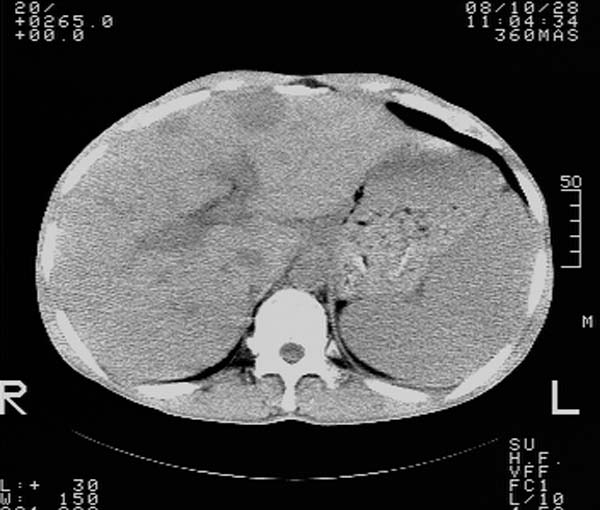

m,65y。半年前发现颈小结节,逐渐增多增大,现双侧耳后、颌下及颈部表浅淋巴肿大。胸片示双肺门增大。外院曾穿刺诊断为淋巴结核。在我科作胸腹部ct,我们觉得外院病检有误。现将图像上传请战友讨论。

纵隔内及腹膜后广泛淋巴结肿大,脾大,肝内似可见低密度影,结合病史半年前发现颈小结节,逐渐增多增大,现双侧耳后、颌下及颈部表浅淋巴肿大。考虑淋巴瘤。

我们也是首先考虑淋巴瘤。只是外院病检报告是结核。让人迷惑。肝左叶多发低密度占位,没增强不好定论。

纵隔,双肺门腹膜后多发淋巴结重大,非融合,肝脾轻度肿大,双肺野弥漫性小结节;考虑淋巴瘤,结节病可能性

纵隔内,双肺门、腋窝及腹膜后多发肿大淋巴结影,肺内小结节影,肝脾体积增大,支持淋巴瘤。肝内多发低密度影,考虑小囊肿。

考虑淋巴瘤肺、肝内转移,脾脏肿大。

纵隔内,双肺门、腹膜后多发肿大淋巴结影及颈部淋巴结肿大,肝脾体积大.结合临床,淋巴瘤可能性大。